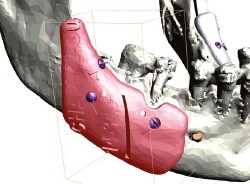

Article réservé à nos abonnés Chirurgie orthognathique guidée

Filière numérique, protocole Phase initiale d’acquisition et de traitement des données natives (segmentation)Elle est enclenchée une fois terminée la préparation...

Article réservé à nos abonnés Cas de classe III squelettique traité avec le système BAM

Cependant, la pose des plaques a été difficile du fait de la finesse du contrefort zygomatique et du peu de...